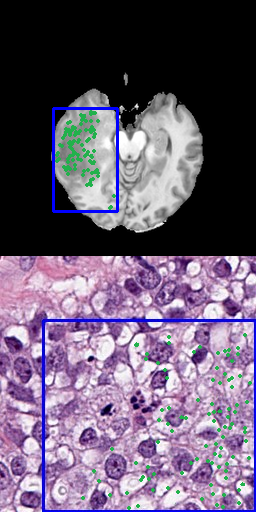

One approach is to use several positive points as input data that represent the goal label [8]. Using points as input is a precise method, allowing to preserve fine segmentation details but requires more annotation effort. When large areas are annotated, this is especially problematic. Figure 3 shows samples for using 3, 10, 50 or 100 points for the radiology and pathology data.

Refer to caption

(a) 3 positive points

(b) 10 positive points

(c) 50 positive points

(d) 100 positive points

Figure 3: Results for different number of positive points without bounding box